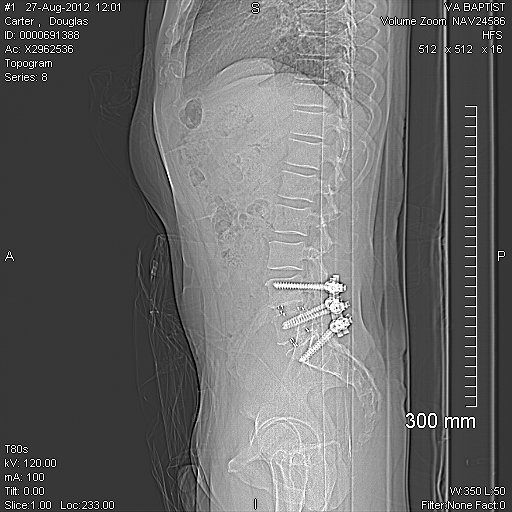

I hurt mine in 1985 and had a bulged disk. I fought it until 97 and had the disk trimmed off the nerve. It never got better. I was young and I was doing things you should not be doing I guess and it never healed. In 2001 all the fluid leaked out of the sack and I got bad bone spurs from that. In 2006 I had another surg. where they replaced a disk installed 6 screws and 2 plates to kinda fuze everything together. I have been through years and years of rehab and for me the pool therapy help me the most. I was on methadone, oxey and what ever I could get and got amuned to it all. Now here it is 27 years later and now I have another disk trying to come out over top of the plate that is there now. I have always been a very small man. I am 5'8 @ 160 lbs and it seems no matter what I do nothing helps. I like sixpack got the sleep number bed and I do sleep a little better. Of course I have to take pills to do that. I hate to have to take pill. I have only got to ride my bike once all summer and have been trying to sell it as well. Not trying to be a downer but I hardly ever here of any back trouble getting better. Maybe it was just my Dr's Have you checked into lazier surg? I think that is the way to go. My scar always tingles and with the lazier it is very small cut and you walk out that day. Just a thought. I am now thinking of trying some testosterone shots to see if I can get the energy to work out again to see if that helps. I do trust in God that one day I will be better and I really wish you the best. What every you decide take your time to heal and always be aware of you back what ever you do. Here is what mine looks like now